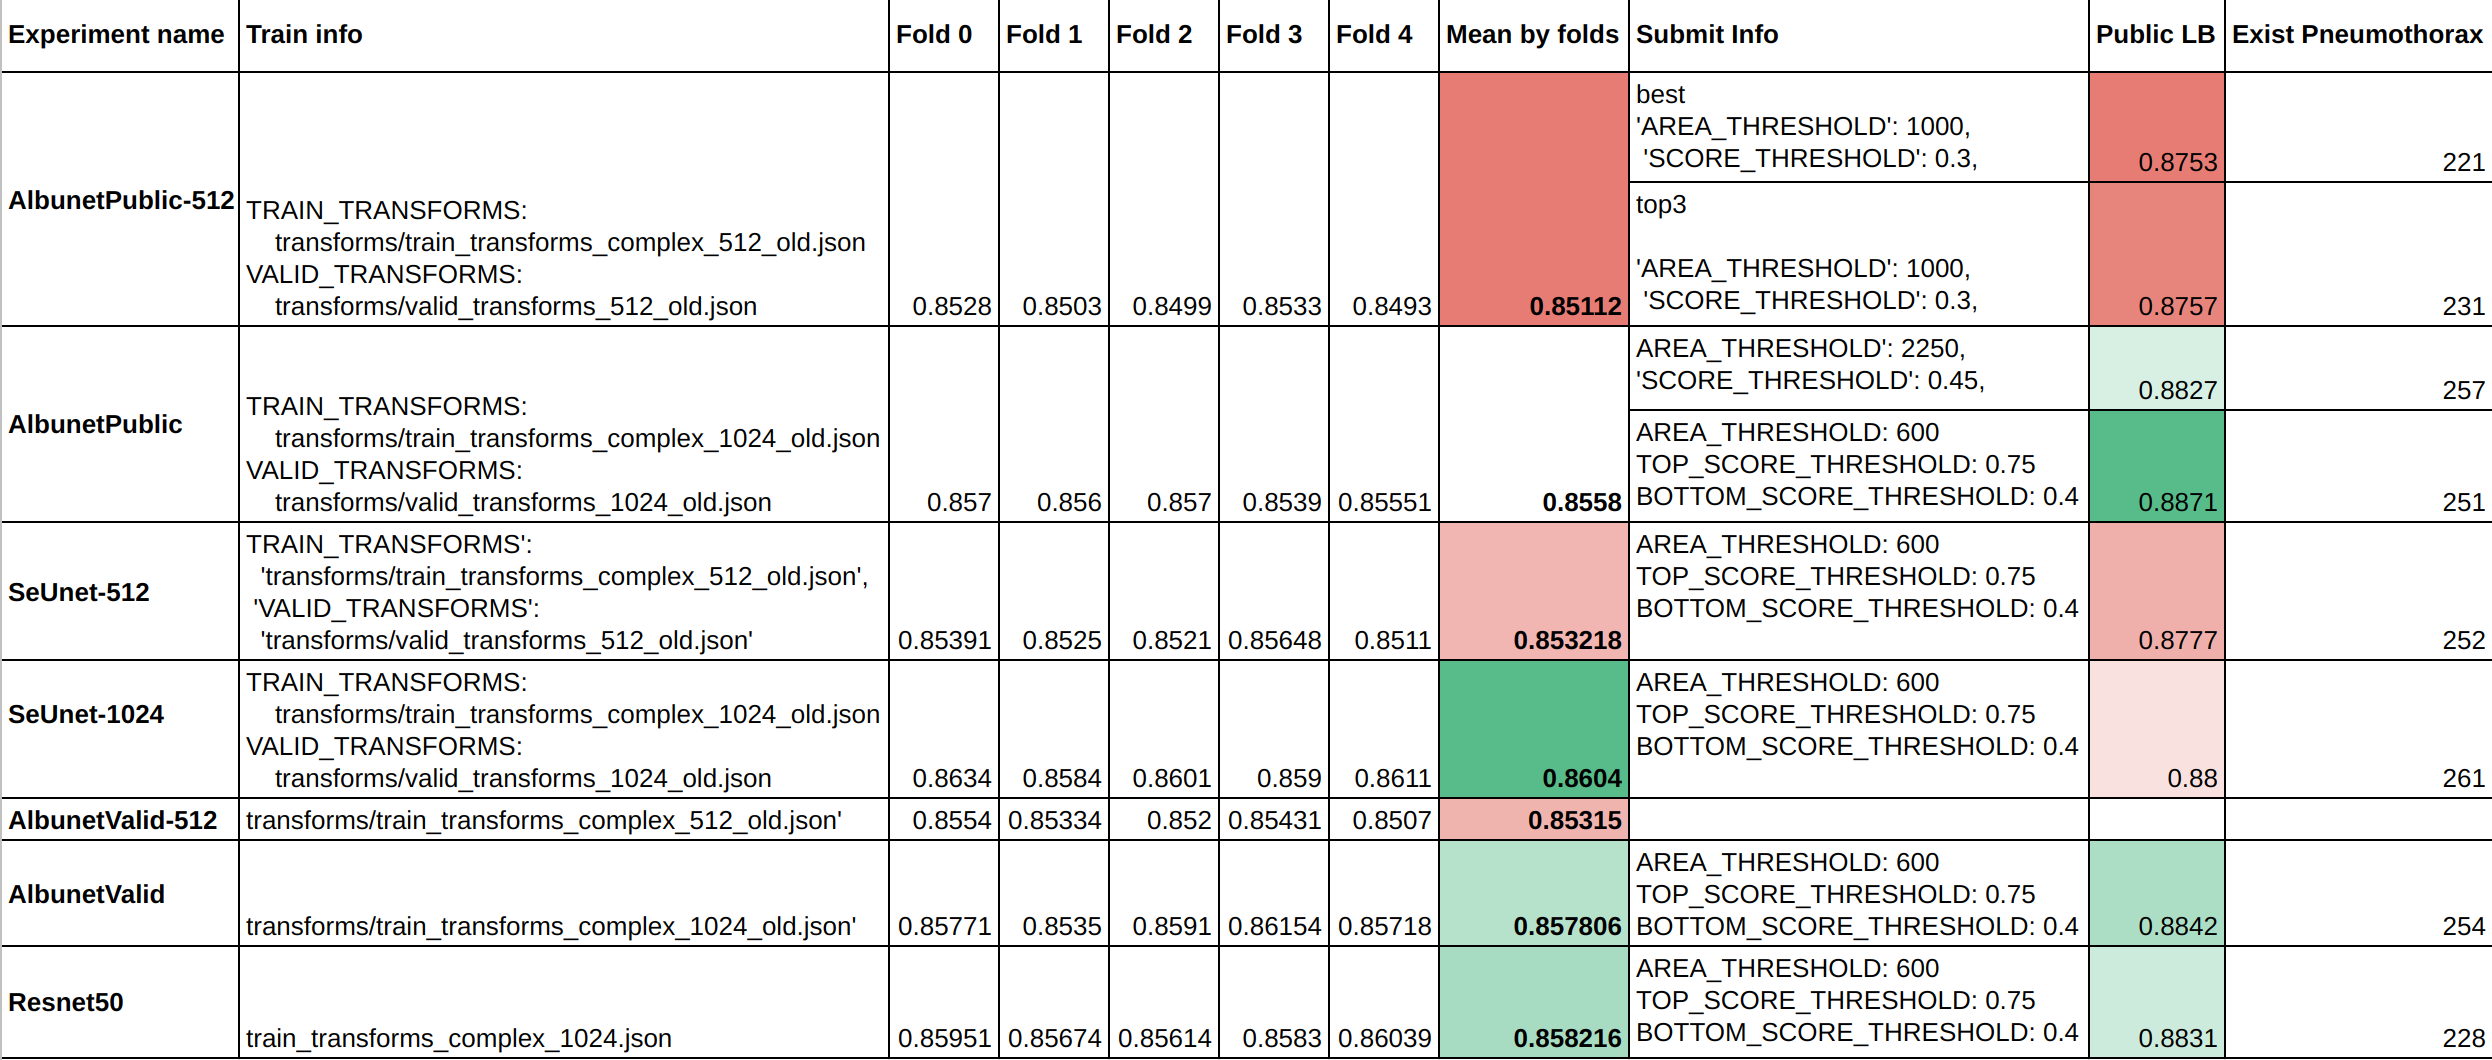

6.2 Inference

作者采用五折交叉验证训练模型,并选择每一个fold的top3个模型的结果求平均输出最终的mask。这里的求平均每个像素点的概率求平均。模型的最终效果如下表:

NOTE:

-

albunet_public - best model for Public Leaderboard

-

albunet_valid - best resnet34 model on validation

-

seunet - best seresnext50 model on validation

-

resnet50 - best resnet50 model on validation